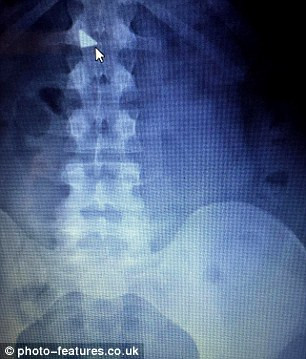

Hình chụp X-quang cho thấy mẩu dao rọc giấy nằm trong bụng anh

Sau khi chụp X-quang, các bác sỹ phát hiện lưỡi dao nằm trong bụng của anh. Các bác sỹ cho biết, rất may mắn vì lưỡi dao sắc nhọn chưa cắt đứt cổ họng hay dạ dày của anh.